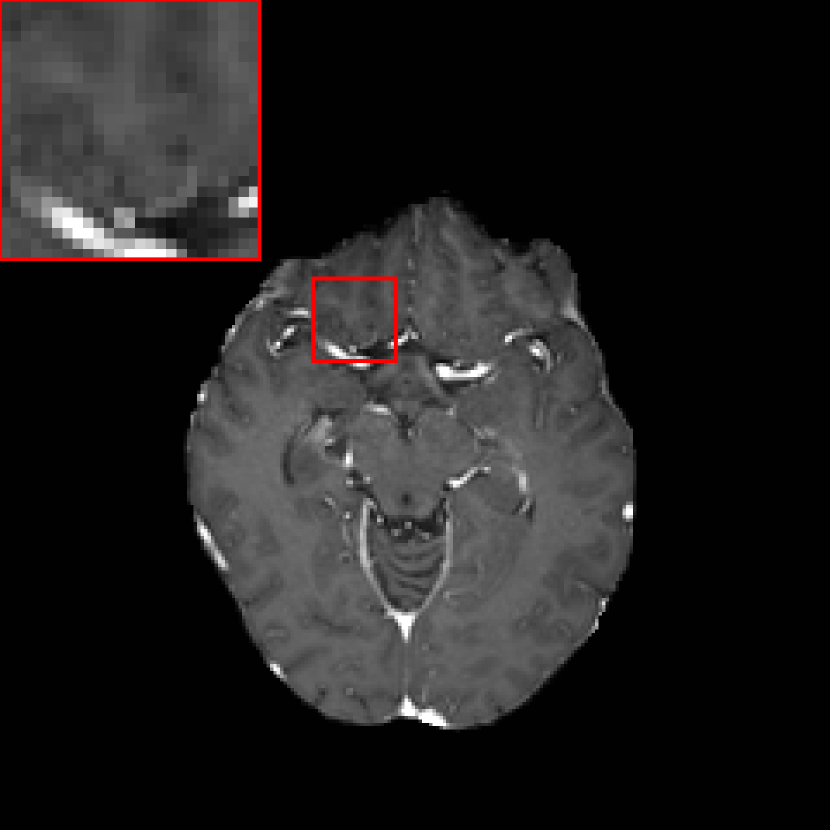

In contrast-enhanced MRI images with 3D volumetric gradient echo imaging (e.g., BRAVO, GE Healthcare; MPRAGE, Siemens Healthcare; 3D TFE; Philips Healthcare) 36, many structures such as blood vessels are also enhanced by contrast agents. Hence, they have similar appearance to metastases in the regard to intensity, shape, and size in 2D intersectional planes. As a consequence, it is very challenging for human experts to distinguish them. BM differ from blood vessels in several aspects. One is that although they appear similar in 2D intersectional planes, they have distinct morphological appearance in 3D space. For example, enhanced vascular structures are tube-like structures with bifurcations, while the majority of BM are sphere-like structures 37. Therefore, 3D neural networks are advantageous over 2D networks to extract 3D features. In addition, BM have relatively larger morphological changes over time than normal tissues. Without treatment BM volume size typically grows faster than normal tissues due to the high proliferation rate of tumor cells. With treatment BM volume sizes change depending on treatment response, for example, volume size decreases in regression, increases in progression, and oscillates (increases first and later decreases) in pseudo-progression 38. In radiation therapy, patients have regular follow-up MRI scans in approximately every 4-6 weeks. Therefore, by comparing two images acquired from two time points, if a high contrast structure emerges or grows, this structure has high confidence to be a metastasis. To integrate such temporal prior information in deep learning, two potential ways are possible: using the temporal prior volume as an additional input channel or as an additional input path. As anatomical structures imaged at different time points cannot be perfectly registered to the same position, using temporal prior volumes as an additional channel will result in a high FP rate. An example is displayed in Fig. 2, where a normal tissue region indicated by the arrow in Fig. 2(b) is segmented incorrectly as a metastasis. Such mis-segmentation is mainly caused by the imperfect registration, since high intensity difference is observed in the corresponding region of the difference image (Fig. 2(c)). To avoid such problem, in this work we propose to put the temporal prior volume as an additional input path, where features from two time points are merged at deep layers. For distinction, the modified DeepMedic architecture is called DeepMedic+ in this work. The overall DeepMedic+ architecture is displayed in Fig. 3, where the normal resolution subvolumes from both the prior and main datasets as well as two low resolution subvolumes from the main dataset are fed into DeepMedic+. Note that for volumes without any temporal prior, an empty prior volume with zero values is used.

Figure 2: Exemplary images acquired from different time points: (a) temporal prior image; (b) current main image, where the contour indicated by the arrow is segmented incorrectly as a metastasis by a neural network that used the prior image as an additional channel as opposed to an additional pathway; (c) difference between (a) and (b), where the bright region indicated by the arrow is the main cause for the incorrect segmentation.

II.C. Temporal prior path

Refer to caption

(a) Prior image

(b) Main image

(c) Difference image